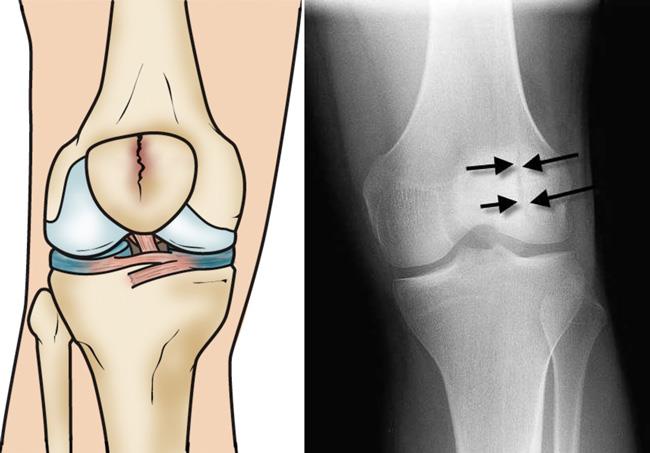

Patellar Fractures (Broken Kneecap

Patellar Fractures (Broken Kneecap

Patella Fracture | Reno Orthopedic Center direct fall on knee cap

patella hairline fracture? - Quora direct fall on knee cap